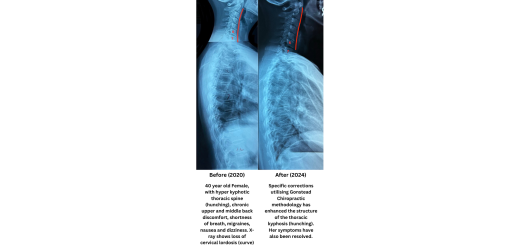

Numbness of hands and fingers